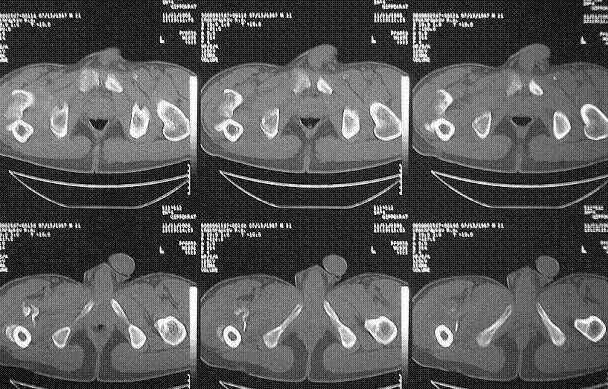

Уважаемые коллеги! Нужен совет. Больной Х., 21 год, ДЗ: ложный сустав вертельной области

правого бедра. Травма 8 мес. назад, ДТП, получил закрытый межвертельный перелом правого

бедра. Лечился в городской больнице одного из городов-спутников г. Караганды скелетным

вытяжением в течение 3 недель, затем кокситной гипсовой повязкой 2 мес.

В настоящее время имеется укорочение конечности на 7 см, умеренная

боль в вертельной области; ходит без костылей, полностью нагружая

больную конечность, при нагрузке отмечается смещение дистального

отломка проксимально примерно на 1,0 см.; объем движений в коленном

суставе сохранен; при пальпации отломков боли нет, умеренная

патологическая подвижность.